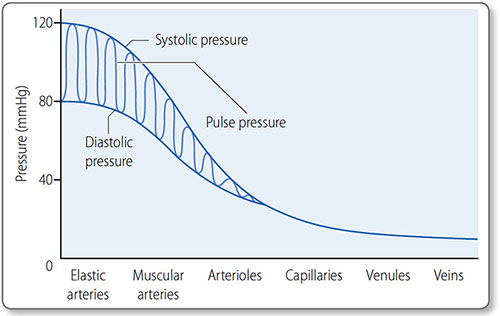

Elastic arteries

These are the major proximal arteries: the aorta and the brachiocephalic, carotid, subclavian, iliac and pulmonary arteries. Their tunica media contain many elastic fibers, which convert the intermittent, pulsatile blood flow from heart contraction into the continuous flow allowing constant tissue perfusion. They absorb energy during systole and discharge it in diastole.

57Maximum blood pressure is reached during systole, and the minimum occurs in diastole. Although the heart is an intermittent pump, blood pressure is maintained during diastole by elastic recoil of the large arteries (Figure 1.35). Blood pressure declines the more distal a vessel is from the left ventricle, as flow energy is lost via friction and resistance decreases.

Figure 1.35: The first vessels in the arterial tree, the elastic and muscular arteries, transmit blood pressure with minimal loss. Through the arterioles there is a large fall in blood pressure and the pulse pressure falls until it is eventually lost.